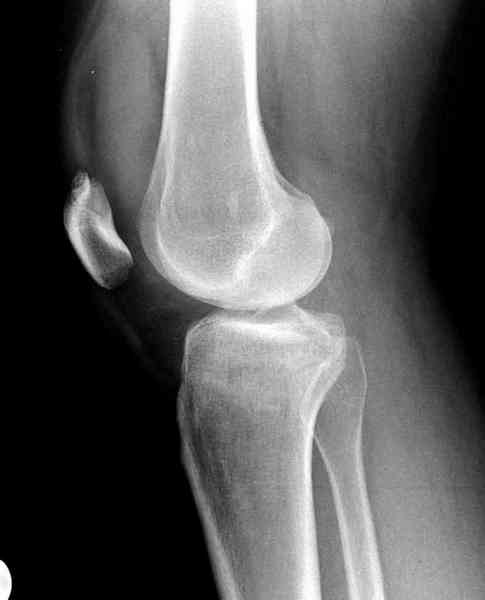

>"мыщелок левой голени будет прооперирован - репозиция, синтез пластиной с костной пластикой, при необходимости удаление повреждённой части мениска"

Для внутрисуставных переломов необходимо идеальное сопоставление, а такая задача без КТ срезов усложнится. Только КТ надо делать после дистракции сустава, иначе нельзя получить объективную информацию.

Около 60% переломов тибиал плато характеризуются мягкоткаными повреждениямм - разрывы суставной капсулы, связок и менисков. Мениск повреждается спереди со стороны перелома.

Тактику удаления мениска во время восстановления считаю ошибочной, наоборот, всеми путями надо его сохранить, потому что предупреждает от деформирующего артроза.

Основная задача в лечении околосуставных переломов является создание солидного базиса в субхондральной зоне. Пластина подпорка (Butress) или субхондральные перкутанные шурупы в виде плота (Raft) для ранних движении.